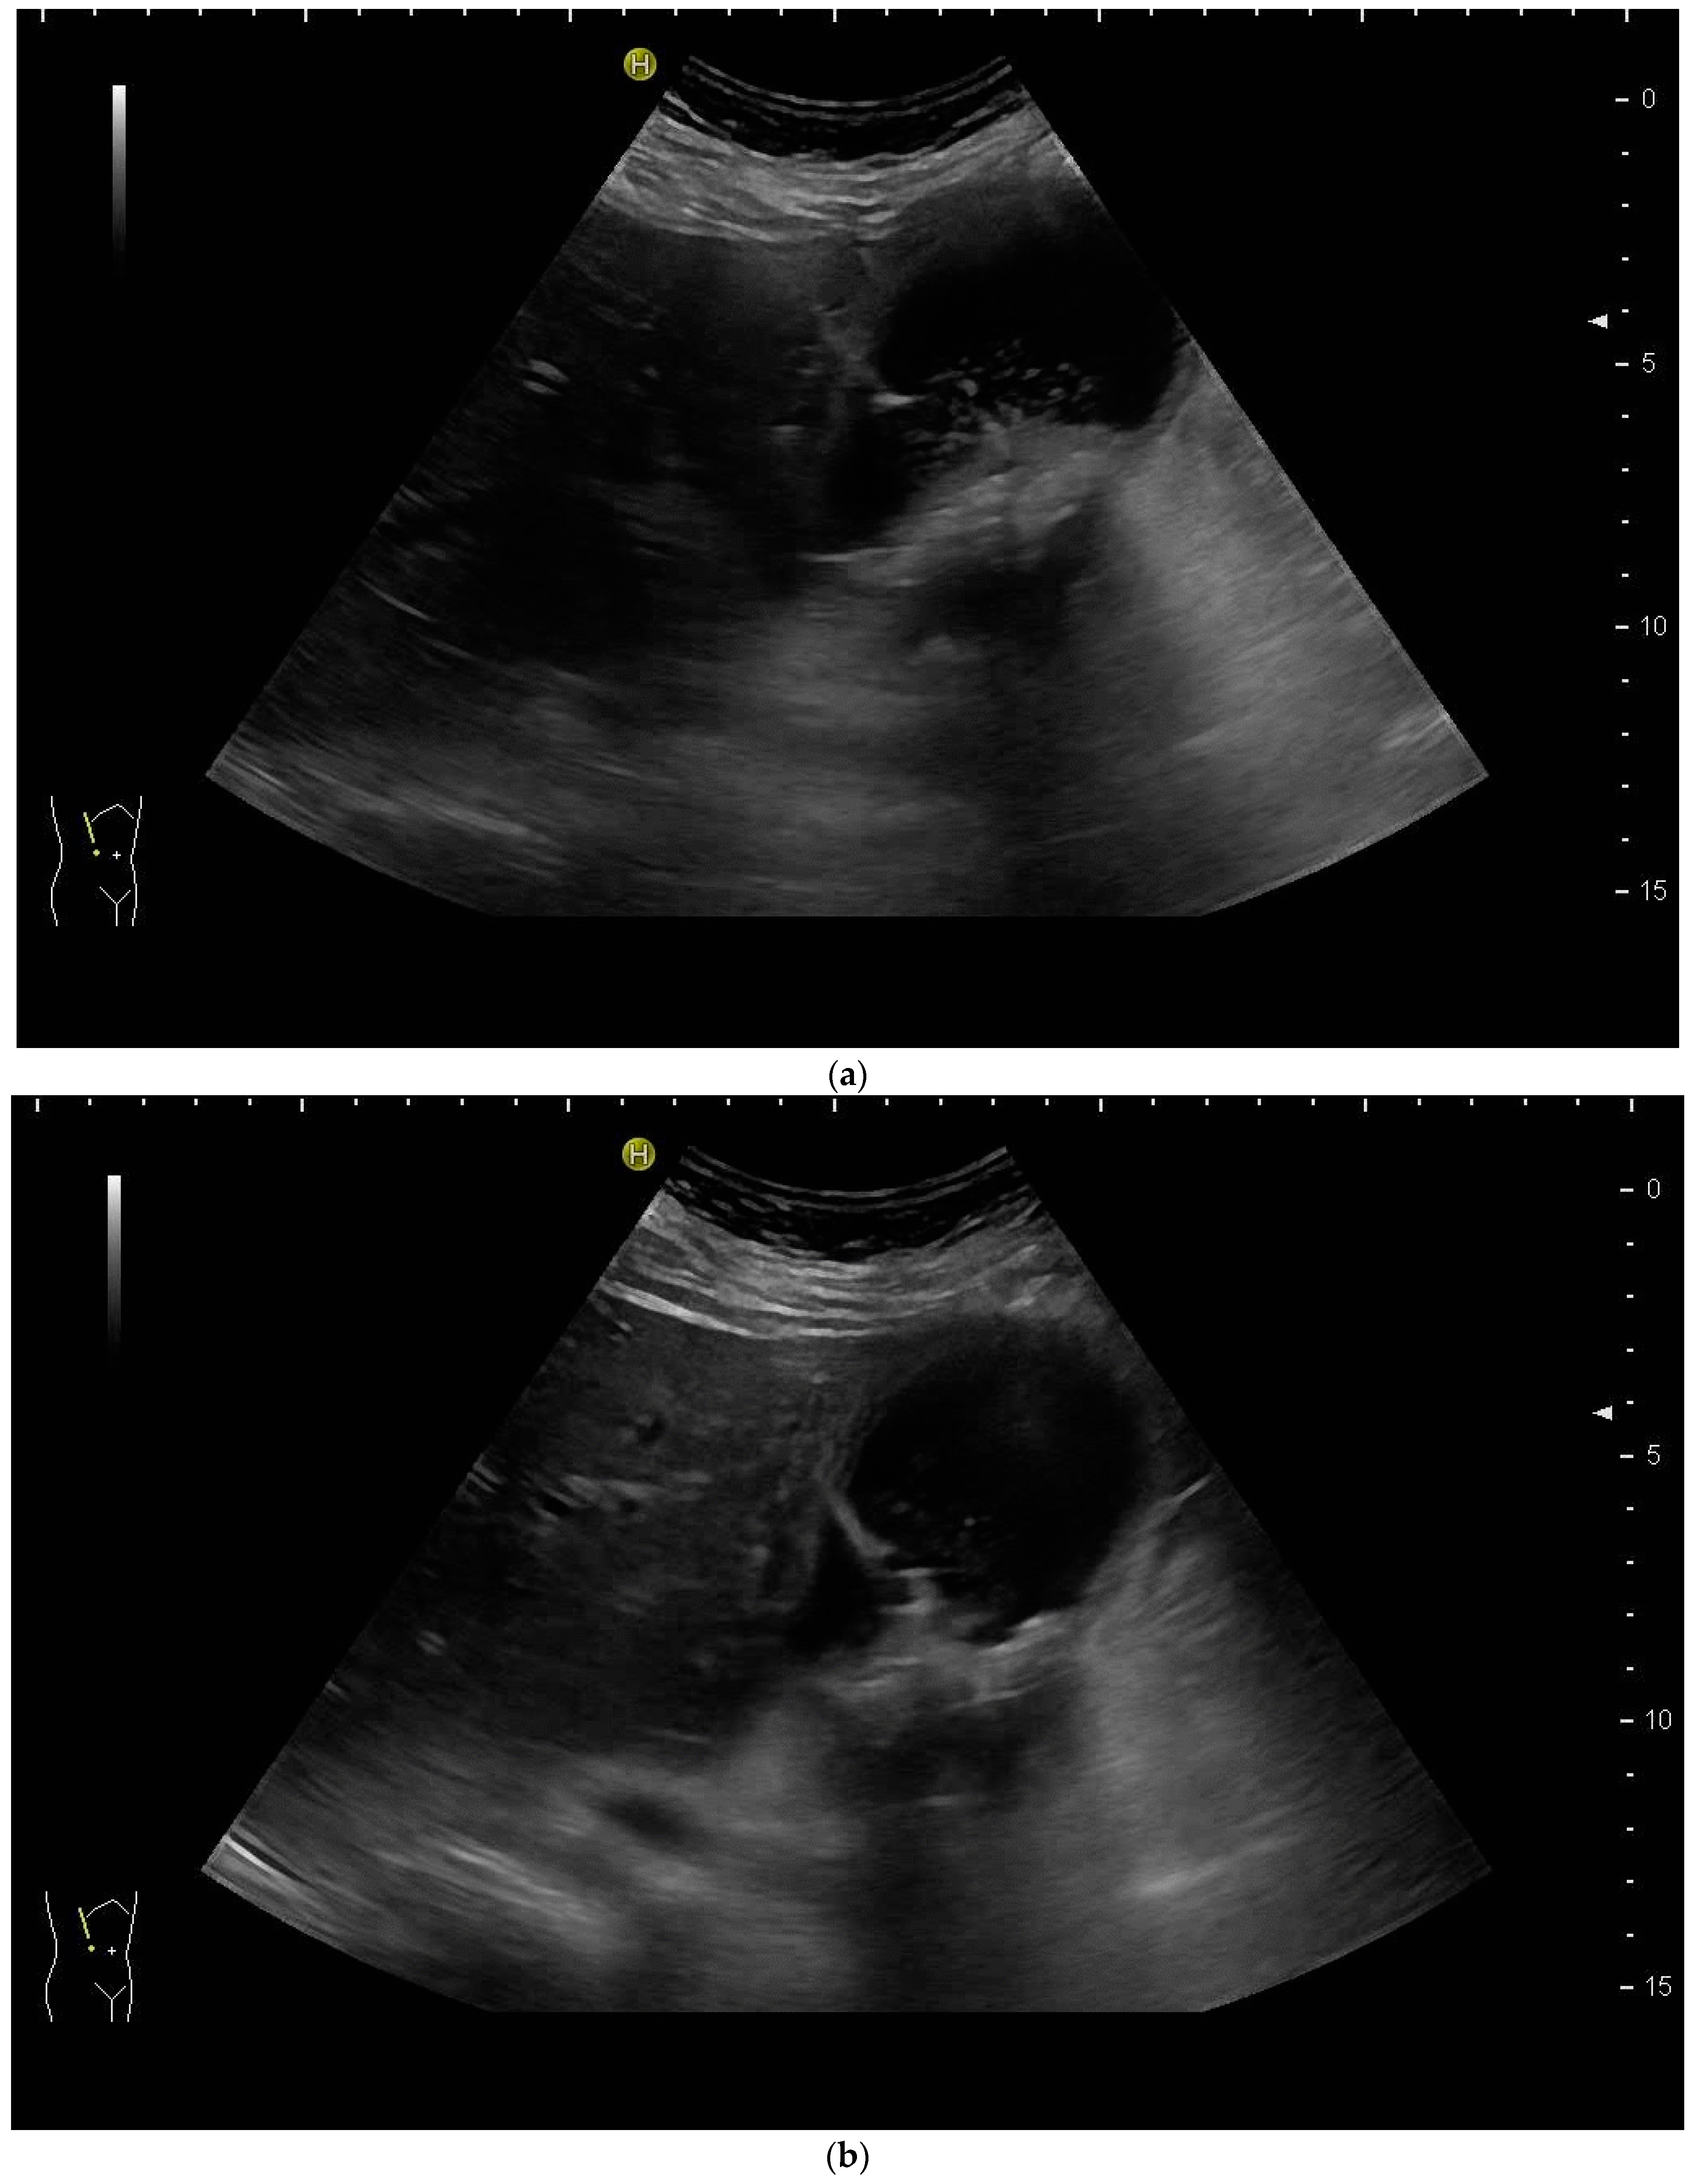

Most authors recommend a transhepatic approach in order to prevent biliary leakage to the abdominal cavity during drainage or after removal of drainage [43,55,56,76,77] (Figure 9).

Figure 9.

(a) Transhepatic puncture of an inflamed gall bladder in the in-plane technique. The Chiba needle is depicted well; (b) A few days later, laparoscopic cholecystectomy was performed. The drainage ran through Segment V of the liver. It was removed without provoking biliary leakage from the liver parenchyma.

The consideration is that a perforation in the hepatic surface of the gallbladder will be covered by the liver tissue after the removal of the drain. However, retrospective analyses comparing the transhepatic route with the transperitoneal (i.e., nontranshepatic) access (Figure 10) report no differences in the complication rates [58,78,79].

Figure 10.

PGBD without passing the liver and using the trocar technique: straightened drainage passes right below the lower liver margin into the gallbladder.

Again, the “in plane” approach is recommended to depict the needle in real time and continuously on its way. This is mandatory because iatrogenic perforation of the posterior gallbladder wall must be avoided. Both the drainage techniques, Seldinger (Figure 11a–c) and trocar (direct puncture, cf. Figure 10), may be used, depending on the physician’s preferences [43,58].